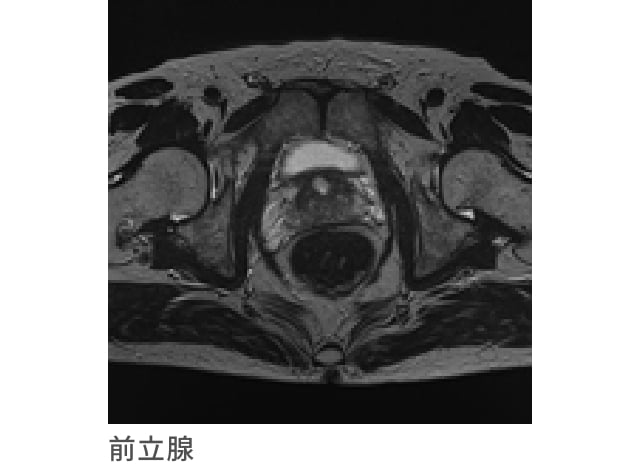

前立腺MRI検査(PSA検査含む)

前立腺肥大、前立腺がんの早期発見に有効な検査です

近年では装置ならびに撮影技術の向上により、微小な早期前立腺がんの発見が可能になりつつあります。

特に見逃しがちであった部位のがんなどを高感度で発見でき、浸襲性(X線被ばくや苦痛など)がなく、且つ、がん病巣を高感度に検出できるのが特長です。

PSA検査と組み合せることで疾病の発見率を高めます。

前立腺がんとは

前立腺がんは、前立腺肥大症とともに、中高年の男性において注意すべきがんのひとつです。

前立腺がんの発生には男性ホルモンが関与しており、加齢によるホルモンバランスの変化が影響していると考えられています。前立腺がんの発生は年々増加傾向にあり、死亡者数も増加しています。

初期症状がほとんどないため、早期に発見し、適切な治療を行うことが大切になります。